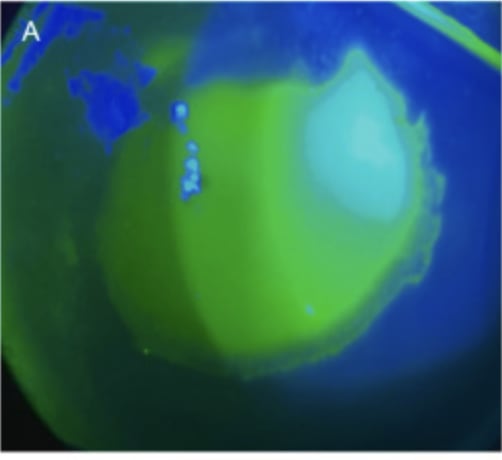

Additionally, should ocular Mpox occur, tecovirimat (an anti-viral medication) and steroid eye drops are shown effective in its direct treatment, according to the paper.